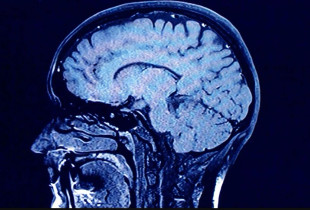

Plakja e trurit

Përse plakja e trurit dallon shumë mes njerëzve

Lifestyle 8 nëntor 2024 12:23

Studim i ri ka zbuluar disa faktorë që mund të ndikojnë në mënyrën se si truri plaket dhe pse disa...